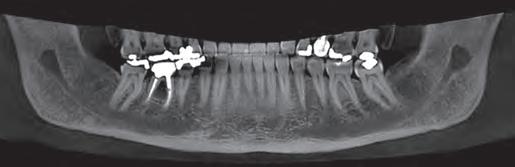

Periapical X-ray confirmed the findings of the clinical examination and root caries was also detected in the distal root of tooth #46, which answered positively to the sensitivity test (Fig.1-2).

Fig. 1: Initial clinical situation.

Fig. 2: Initial X-ray.

Fig. 3: Class II cavity prepared.

Fig. 6: Biodentine™ applied in a Bio Bulk-Fill approach.